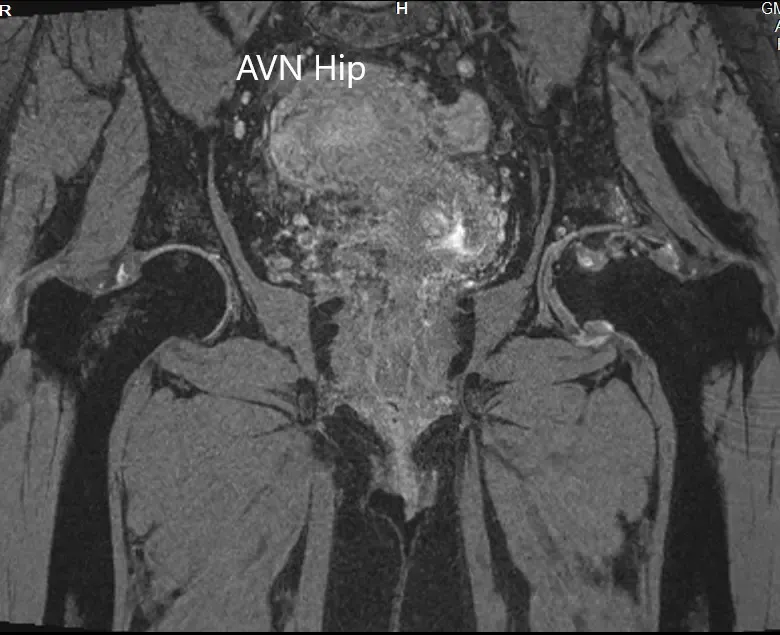

Se realizó una resonancia magnética que mostró una intensidad de señal alterada tanto en T1WI como en T2WI. Hubo un colapso sutil de la cabeza femoral izquierda. Se observó una línea sérpinosa e hiperintensa en T2WI que delimitaba una zona de osteonecrosis en la cabeza femoral izquierda. Esta zona afectaba al compartimento lateral y medial y cubría más del 50% de la superficie de la cabeza.

Se visualizaron cambios osteoartríticos secundarios en forma de reducción del espacio articular anterosuperior y formación de osteófitos. Se observó una pequeña cantidad de líquido en la cavidad articular.

Imagen T1WI de la resonancia magnética que muestra la sección coronal.

Imagen de resonancia magnética T2WI mostrando la sección coronal.